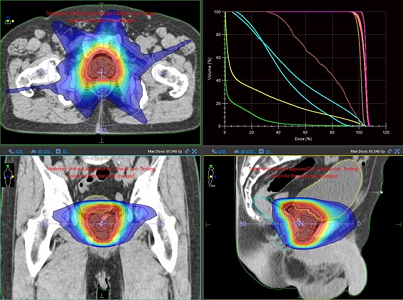

小線源治療には、ラルス(RALS:Remote After Loading System)という専用の医療機器が多く用いられます。この機器を用いて、粒状の小さな放射線源を身体の中に入れ、身体の中から放射線を当てる方法です。そのため、放射線を病変に限局し、かつ集中的に照射できるようになっています。従来は単純X線画像を用いて治療計画を行っていましたが2014年よりCT画像やMR画像を用いた三次元画像誘導密封小線源治療を開始しました。単純X線画像ではわからなかった腫瘍やリスク臓器が可視化できるため、より腫瘍に限局した照射ができリスク臓器の線量を下げることが可能になりました。

放射線治療計画CT

放射線治療の準備として、まず治療計画を立てるためのCTを撮影します。得られたCT画像から放射線治療医師が、病変や周囲正常組織の位置関係を三次元的に正確に同定し、放射線の投与量と照射範囲を厳密に設定することにより、正常組織の影響を最小限に抑え、かつ病変に集中的に放射線を投与できるように照射方法を決定します。